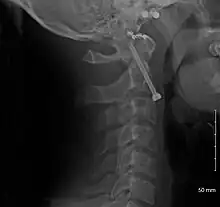

A fracture of the base of the dens as seen on plain X-ray